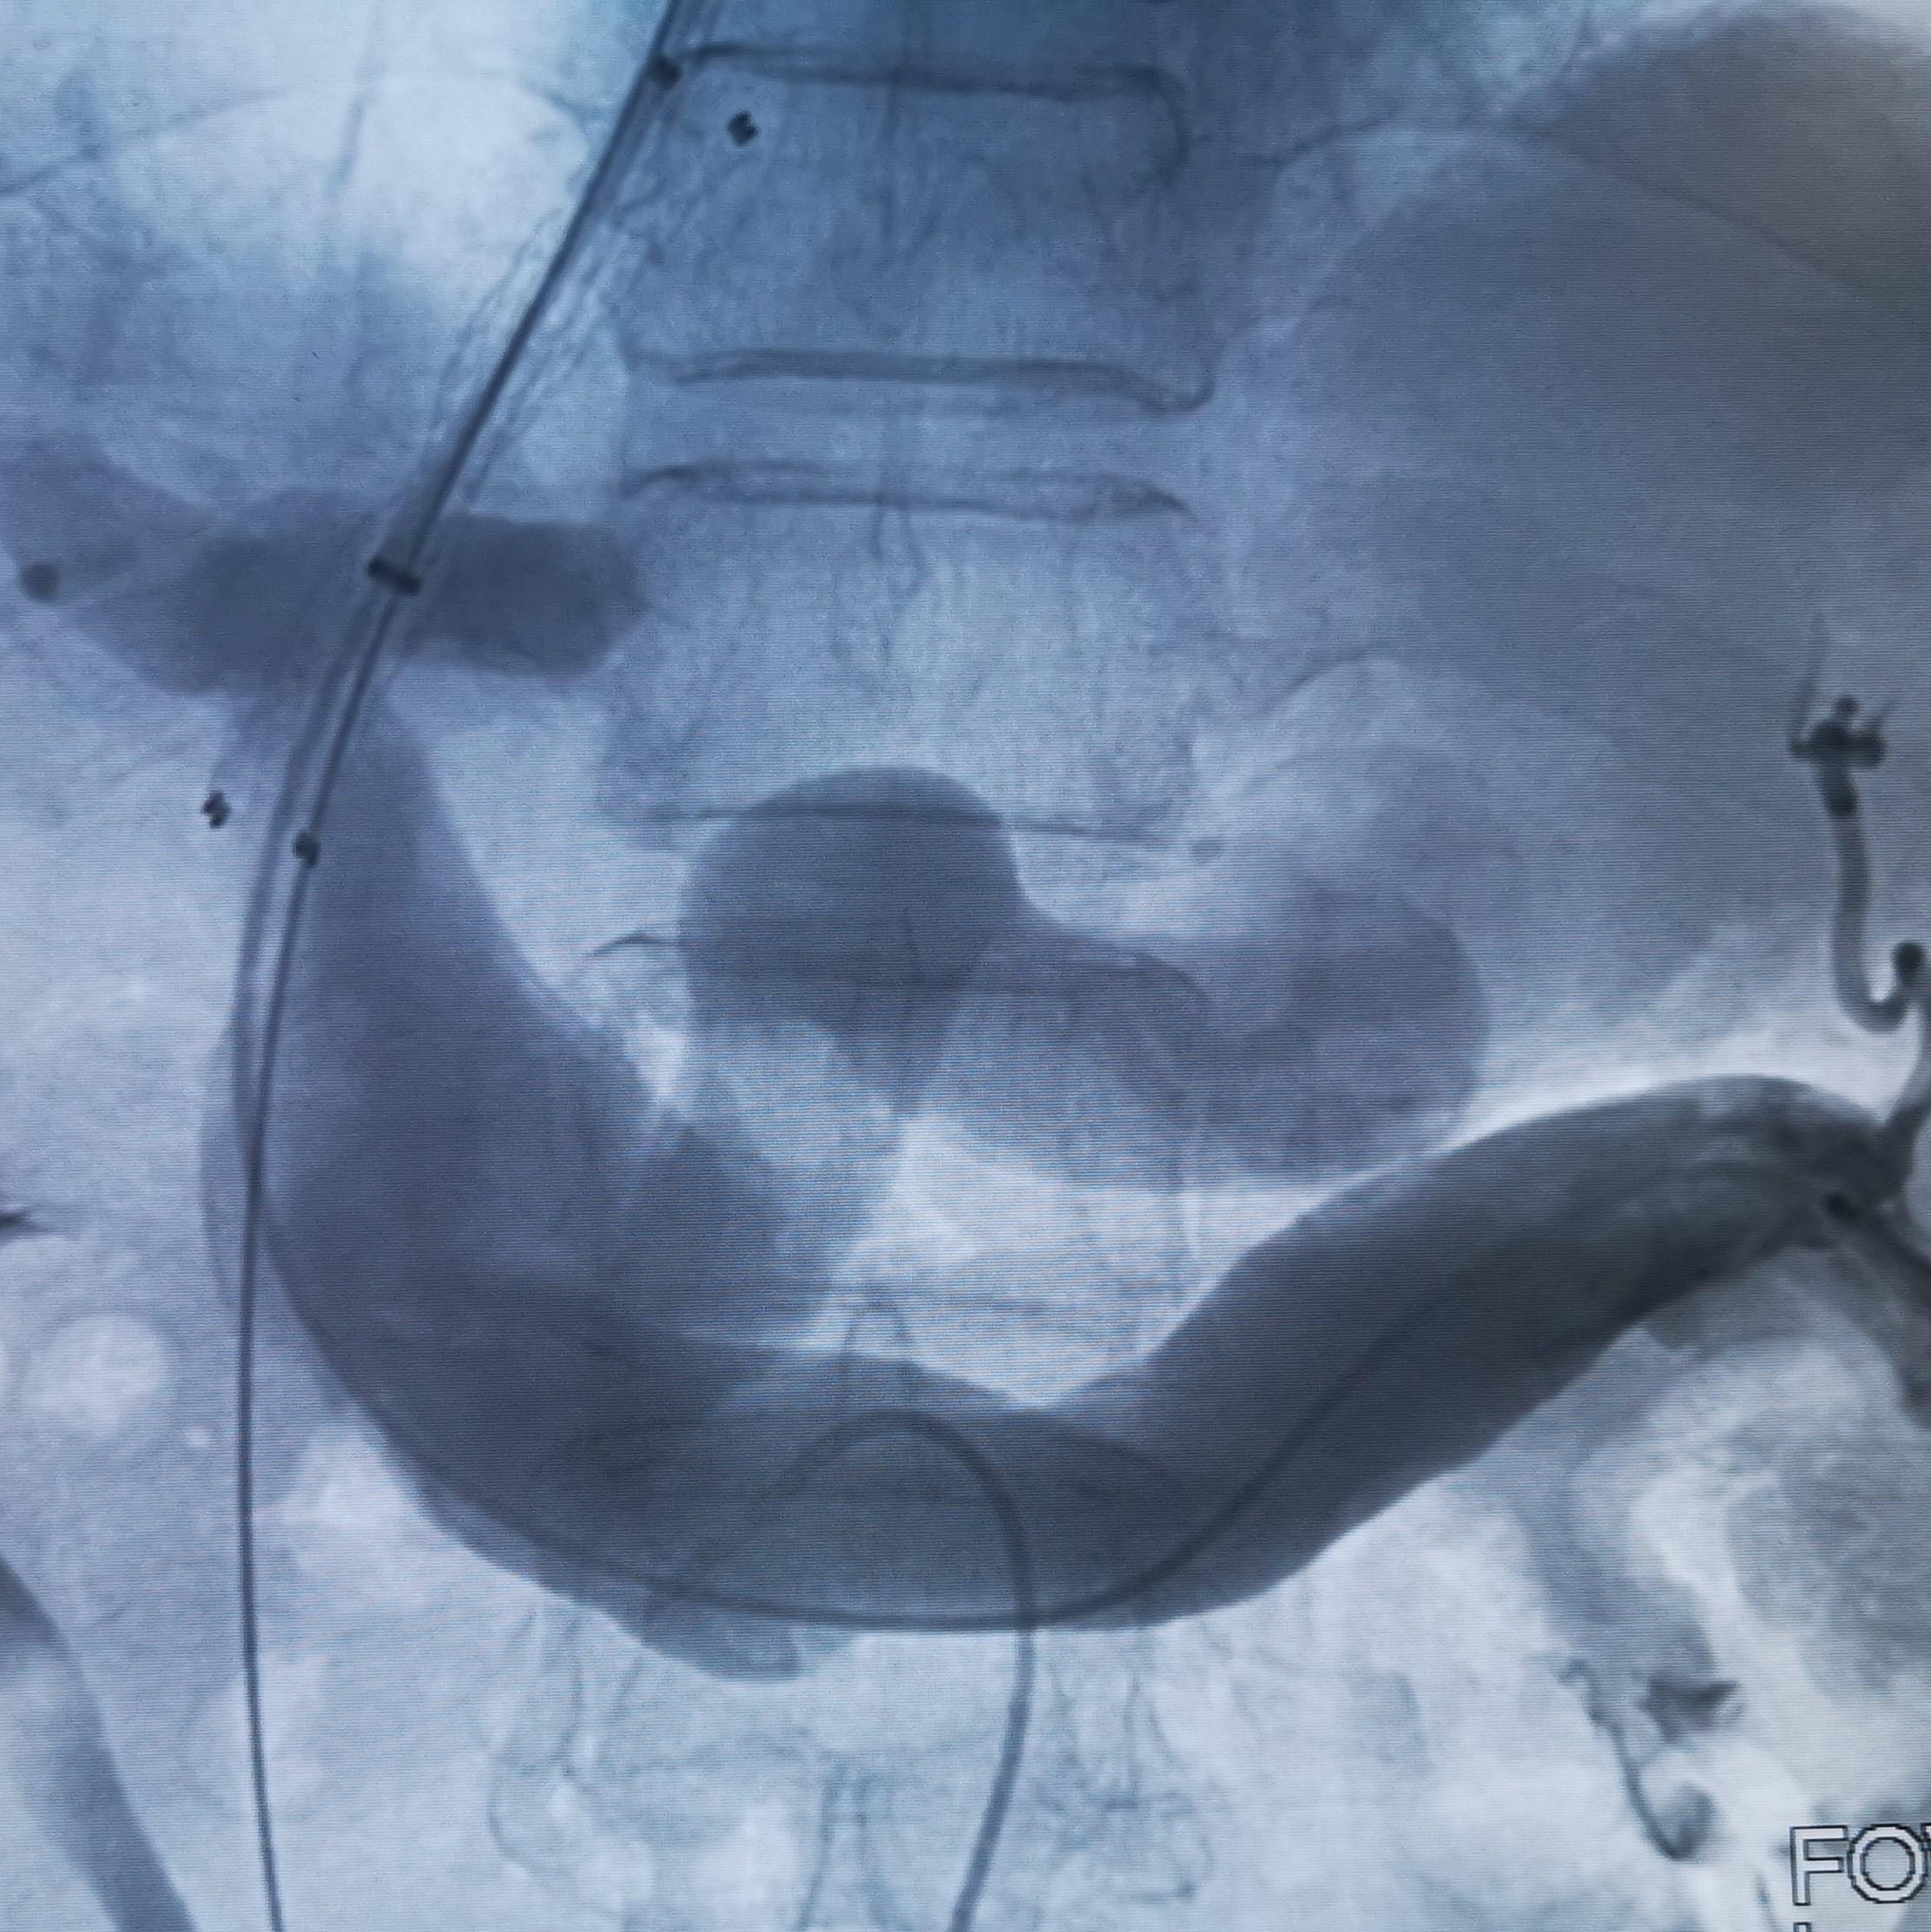

3.术中DSA:

TIPS和食管胃底静脉栓塞术后

经颈静脉门体分流术(TIPS)是在肝静脉和门静脉之间创建引流通路,降低门脉压力的方法。1988年,TIPS首次应用于肝硬化合并静脉曲张出血的治疗。其降低门脉压力效果显著,控制食管胃底静脉曲张破裂出血成功率高,被越来越多应用于肝硬化门脉高压症的治疗。有学者对实施TIPS治疗的食管胃底静脉曲张破裂出血的患者进行观察,发现TIPS出血控制率在90%以上。

这名患者的治疗过程就符合该治疗策略。术前的CT平扫已经显示极度扩张的胃冠状静脉,这在DSA影像上得到证实。2018年患者第二次出血时做的增强CT上已经显示出患者的胃冠状静脉扩张。此时,已经具有行TIPS的指征。在经过3年的变化后,病情是急剧加重。如果出血剧烈、生命体征不平稳,或各种原因导致不能行急诊胃镜的情况下,不要错过TIPS降低门脉压力的机会。